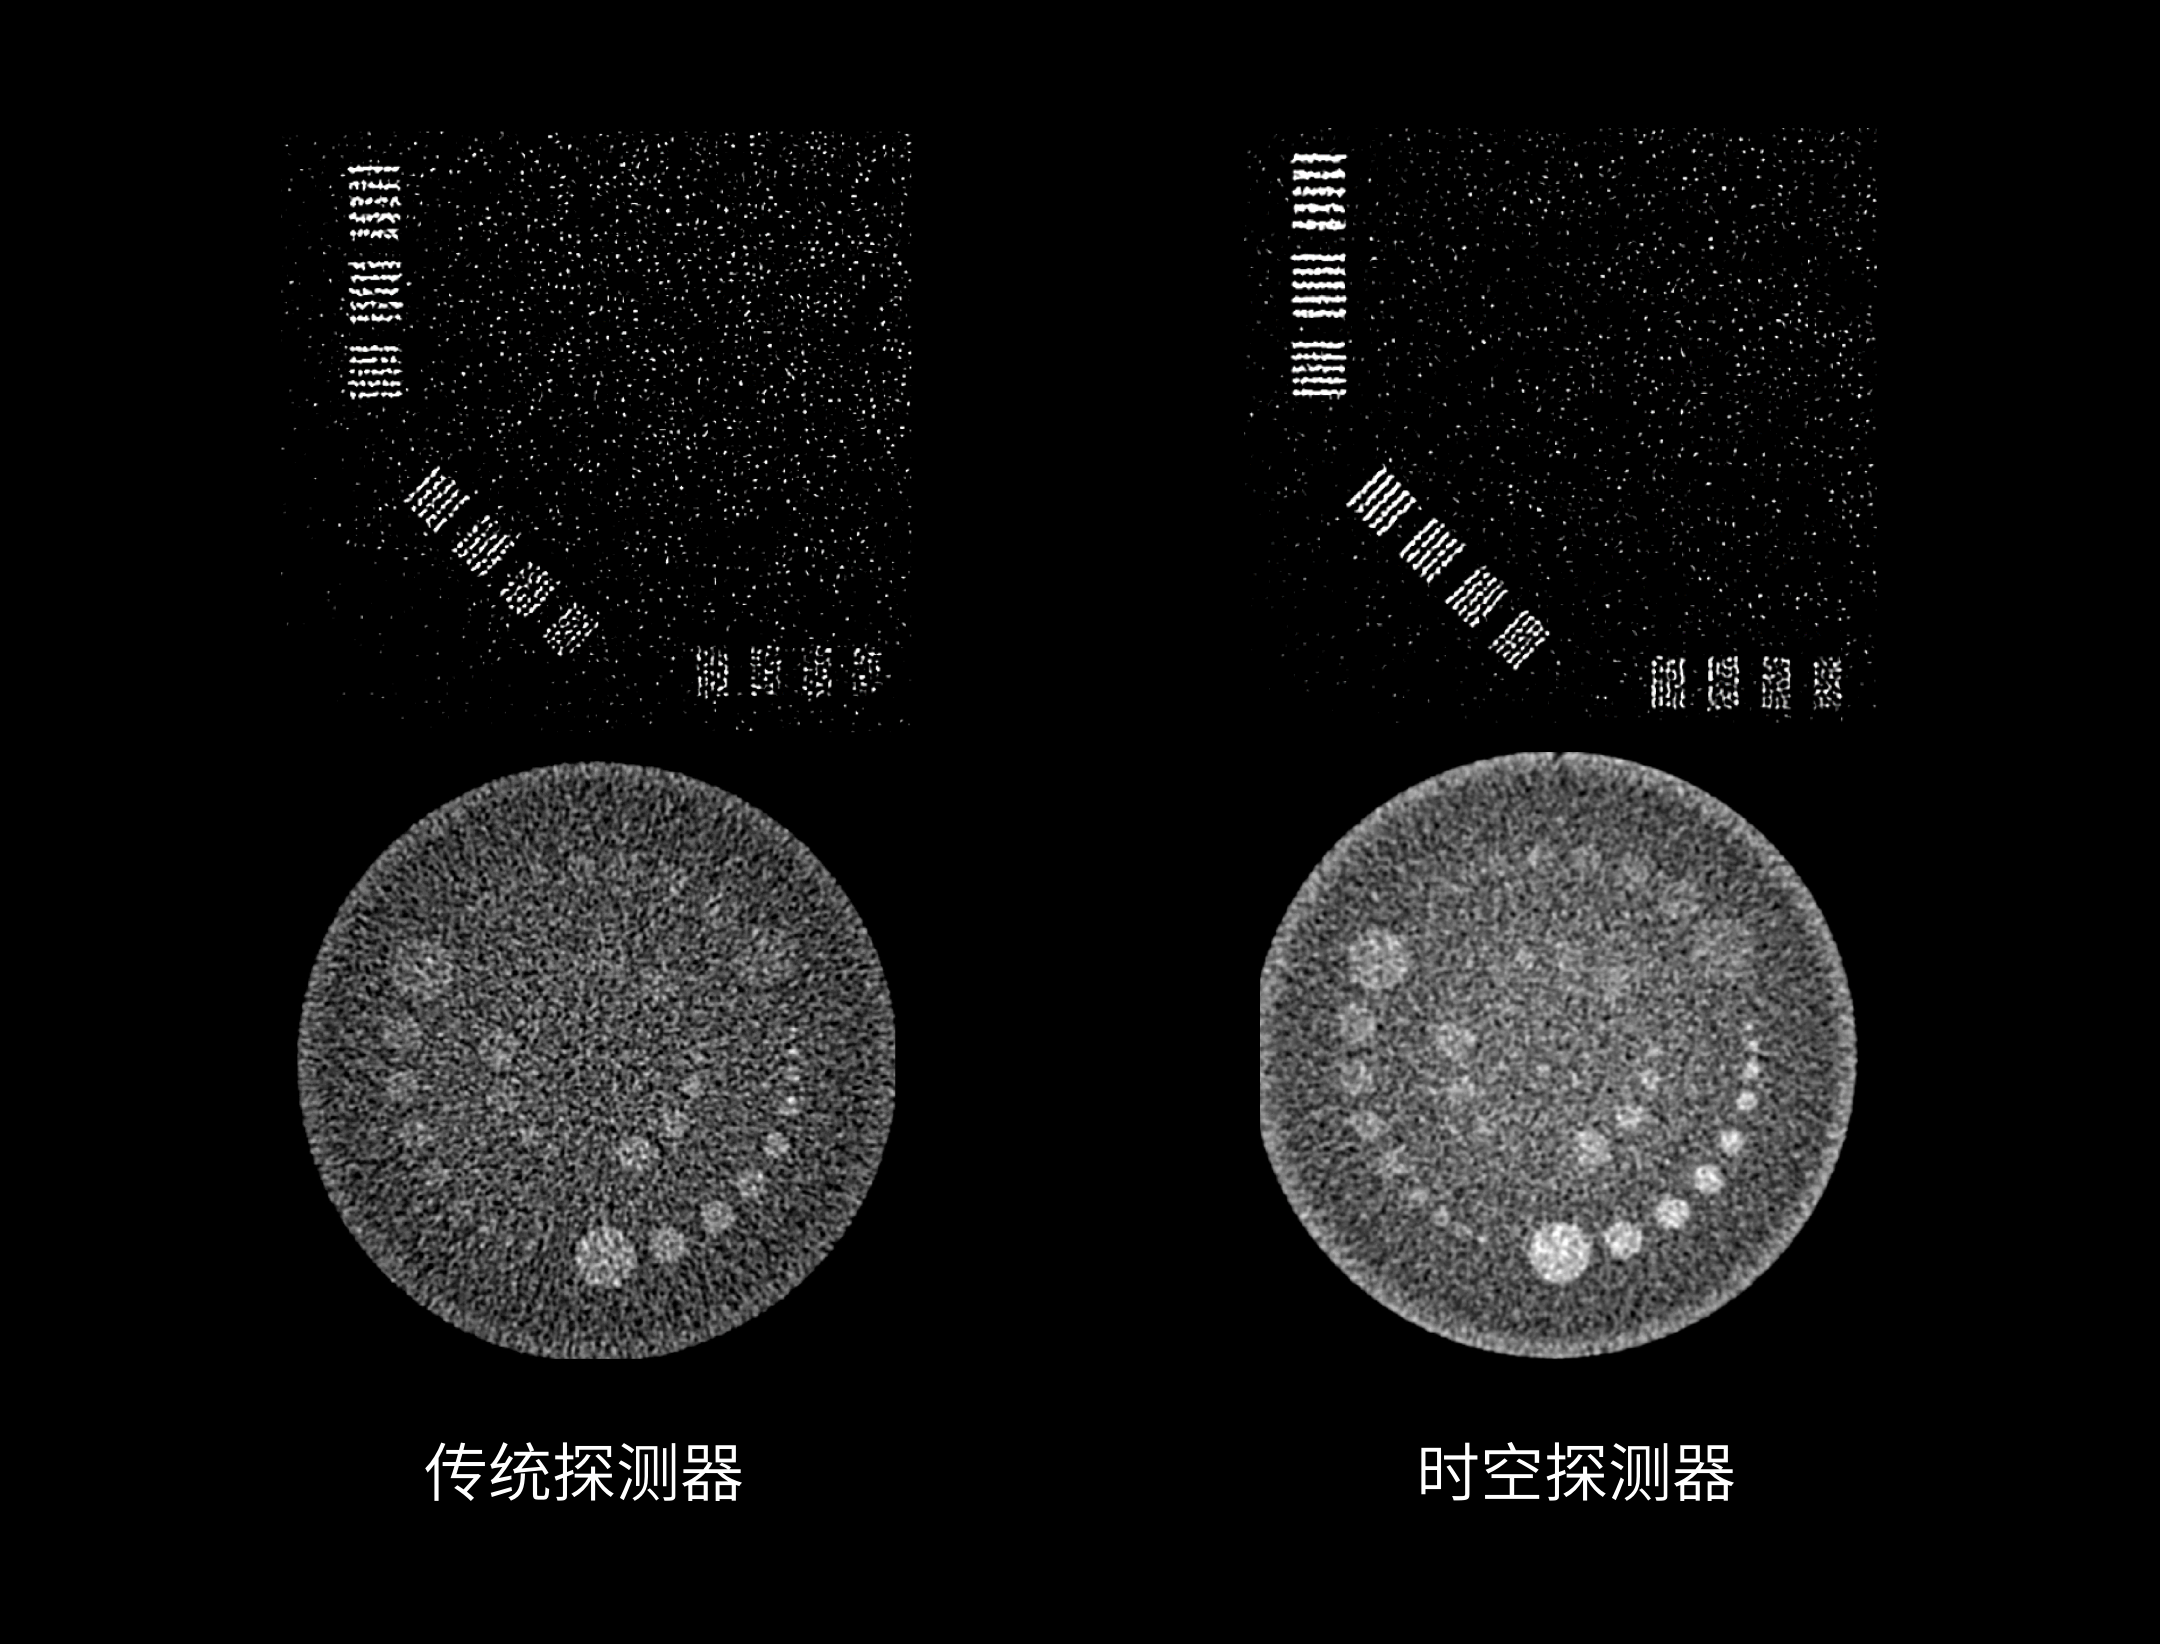

320层宽体时空探测器

一体化3D 防散射光栅技术

采用3D打印精密工艺生产,149760 个不同形态栅格单元应对每个探测器单元,精准对焦X射线焦点全方位遮挡散射光子,显著降低散射对于宽体成像影响。

0.5 mm 精细像素采集

0.5mm精细探测器单元尺寸,有效减少部分容积效应,显著提升图像空间分辨率。